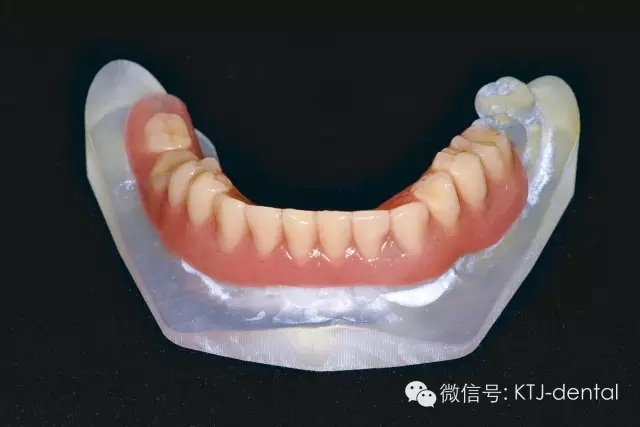

圖5 格萊美種植導(dǎo)板(類型為牙支持式導(dǎo)板)

圖6 標記有基臺位置的3D打印模型,模型用于制作即刻修復(fù)義齒及根據(jù)基臺位置預(yù)先掏空

本病案小結(jié):使用預(yù)成種植套筒冠基臺行無牙合即刻負重手術(shù)操作簡單,效果可靠,臨床應(yīng)用方便快捷。但種植體的平行度是保證此修復(fù)方式成功實施的關(guān)鍵。本病例的CAD CAM手術(shù)導(dǎo)板在應(yīng)用過程中發(fā)揮以下作用:嚴格控制種植體的平行度,避免損傷下牙槽神經(jīng)及頦神經(jīng)(無須翻瓣暴露神經(jīng)),根據(jù)種植體植入深度預(yù)選適當(dāng)?shù)幕_,根據(jù)術(shù)前打印模型預(yù)先調(diào)磨即刻負重義齒。CAD CAM手術(shù)導(dǎo)板的應(yīng)用使得手術(shù)操作有更強的預(yù)期性。在應(yīng)用技巧方面,預(yù)先保留不影響植入位點的牙齒,獲得更為精確的牙支持式的手術(shù)導(dǎo)板,減少了手術(shù)誤差。半程導(dǎo)板配套的器械盒應(yīng)該合理地與相應(yīng)種植系統(tǒng)外科器械配合使用,并根據(jù)骨的質(zhì)地采用相應(yīng)的預(yù)備方式,使得植入位點精確,并獲得良好的初期穩(wěn)定性完成下一步的即刻負重治療。